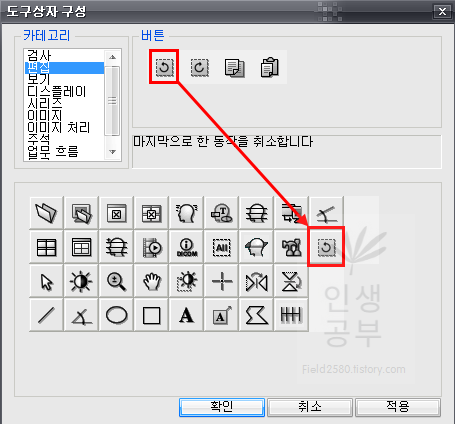

제일 앞에 있는 버튼이 마지막으로 한 동작을 취소합니다 버튼입니다. 버튼을 드래그해서 아래로 끌어다 줍니다.

마지막으로 한 동작을 취소합니다 버튼이 추가 된 것을 확인하실 수 있습니다.

그 후에 2번째 칸에 있는 이전에 취소한 동작을 다시 수행합니다 버튼을 추가해줍니다.